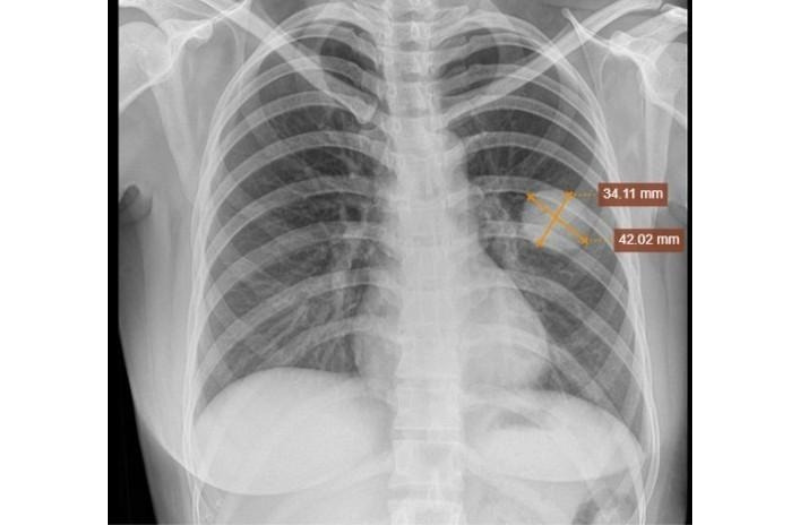

Hình ảnh chụp phổi trái: Nhu mô thùy dưới phổi trái có khối mờ kích thước 34x42mm, bờ đều, sau sinh thiết, hiện không thấy tràn khí màng phổi.